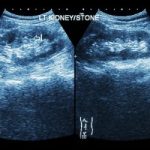

Recurrent kidney stone patients at higher risk of heart disease and osteoporosis

Recurrent kidney stone patients at higher risk of heart disease and osteoporosis

Recurrent kidney stone patients are at a higher risk of heart disease and osteoporosis. The findings suggest that close monitoring of recurring kidney stones could help protect patients from heart-related problems.

Nearly 10 percent of men and seven percent of women will develop kidney stones, and over the last few decades mounting evidence has shown that individuals who have experienced kidney stones have an increased risk of developing other conditions, including hypertension, chronic kidney disease, and heart disease, but the mechanisms involved were long unknown.

The researchers speculate that the rise of heart-related conditions due to recurring kidney stones may be associated with abnormal calcium deposits in the blood vessels. Vascular calcification is strongly correlated with heart-related disease and death. Continue reading…